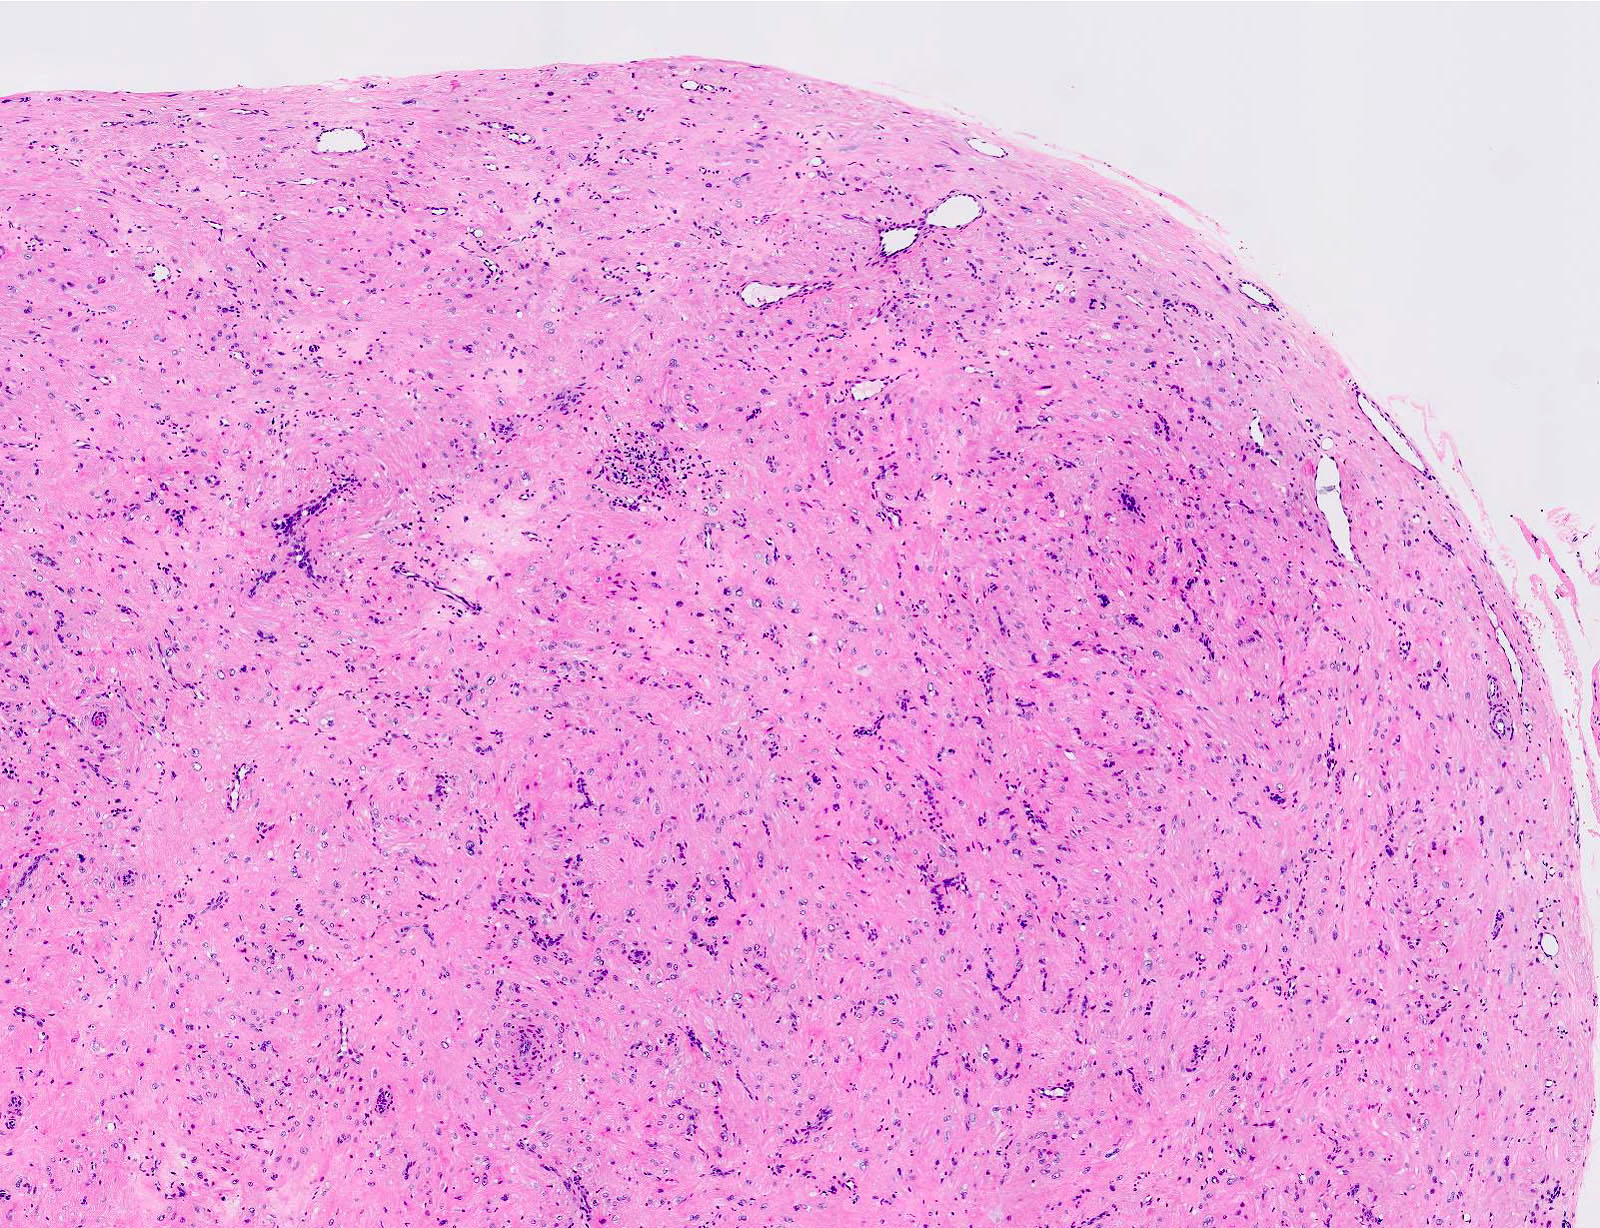

Microscopic (histologic) description

- Encapsulated proliferation of eosinophilic smooth muscle cells with minimal nuclear pleomorphism

- Rounded or slit-like veins with muscular walls present within the tumor (J Cutan Pathol 2017;44:342)

- Tumors can further be classified into 3 subcategories, first described by Morimoto et al:

- Solid type: smooth muscle bundles surround numerous small slit-like channels

- Cavernous type: dilated vascular channels, the walls of which are difficult to distinguish from the intervascular smooth muscle

- Venous type: thick walled vessels that are easily distinguished from the intervascular smooth muscle

Microscopic (histologic) images

Contributed by Ohoud Aljarbou, M.D., Jijgee Munkhdelger, M.D., Ph.D. and Andrey Bychkov, M.D., Ph.D.

A. Angioleiomyoma. A mixture of smooth muscle bundles arranged in small fascicles and intervening vascular channels is noted. The concentric perivascular spindle cell proliferation which is characteristic for myopericytoma is absent. There are no glomus cells seen. Adipocytes are not seen in this image, which makes angiomyolipoma less likely.